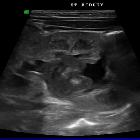

Generally, fungal balls are appreciated as mobile, rounded, heterogeneously hypoechoic masses, although hyperechoic masses have also less frequently been described . No evidence of vascularity is seen within the mass on a Doppler study .